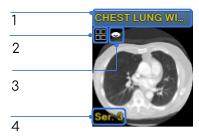

Alapértelmezésben egy fejléc jelenik meg a mini kép fölött, és tartalmazza a sorozat leírás értéket.

Sorozat leírás

Látható a kockában

Nem megtekintett halmaz/kép

Sorozat szám